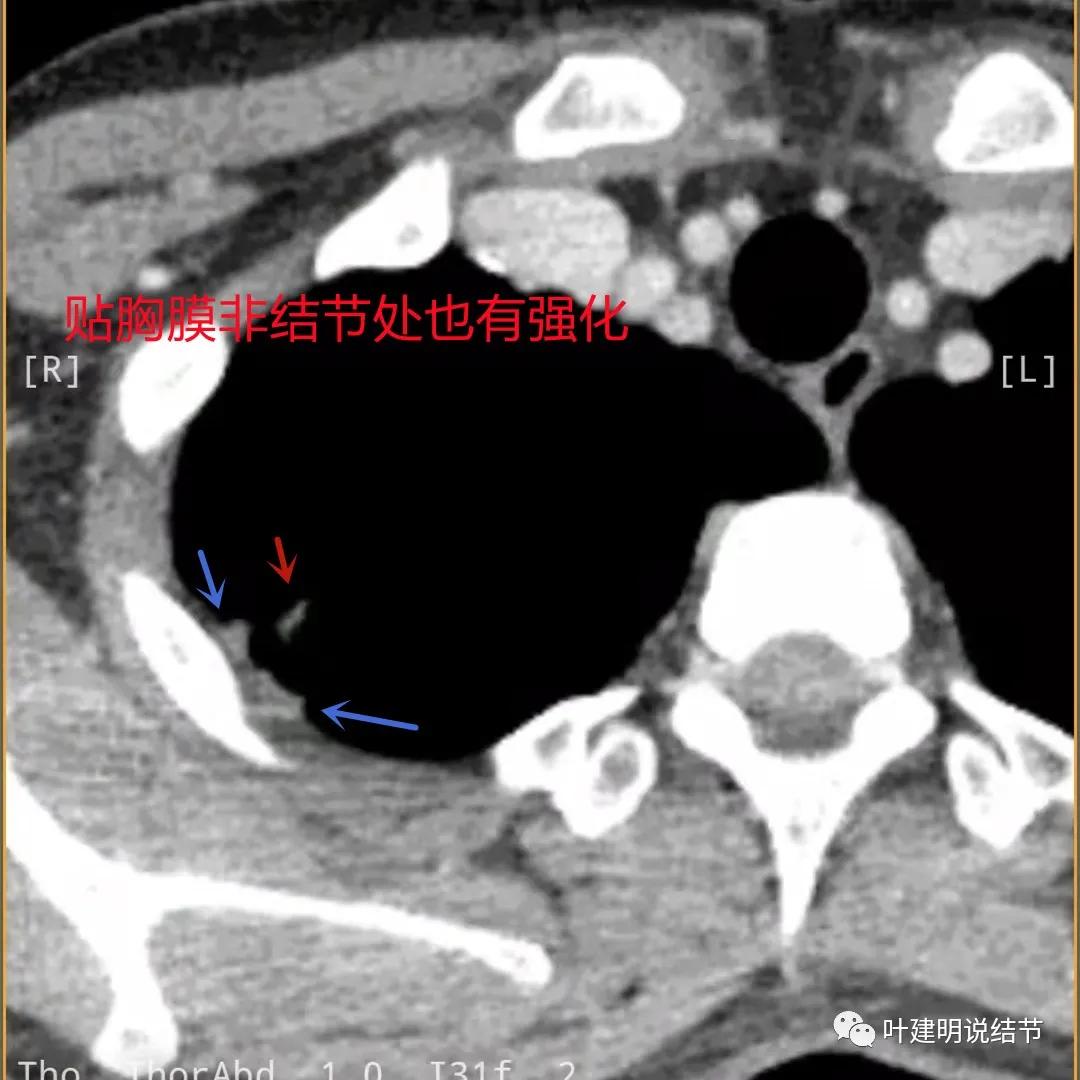

贴胸膜侧也是有强化的,这里可不是结节主病灶所在

薄层影像印象:病灶有明显强化,且邻近胸膜处及部分囊壁区有极低密度区域,考虑干酪样坏死可能性大,肿瘤的坏死可能性小,肿瘤一般要长的比较大,中央缺血性坏死。整体病灶也是觉得散,且邻近胸膜处甚厚。考虑炎性,尤其是肉芽肿性炎伴干酪样坏死可能性大。